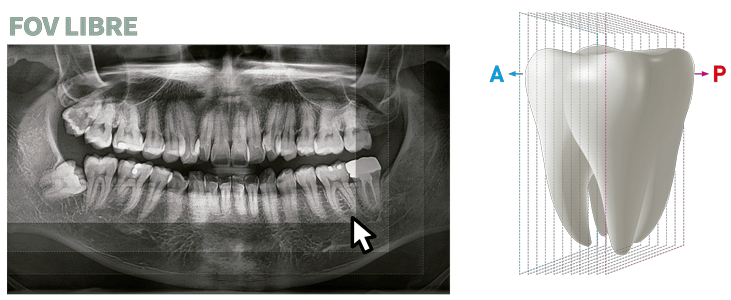

GRAN FOV DE ESCANEO

Green X tiene una amplia gama de campos de visión para que puedas elegir FOV óptimo minimizando la exposición en áreas que no están en la región de interés.

La selección de FOV se adapta a tus necesidades de diagnóstico: 16×15 (opcional), 16×9, 12×9, 8×9, 8×5, 5×5 y 4×4. Estas opciones abarcan toda la región del arco, seno y ATM (izquierda /derecha) y se adapta a la mayoría de los casos de cirugía y cirugía de implantes múltiples.

FUNCIÓN INSIGHT DE SEGUNDA GENERACIÓN

Insight PAN es capaz de tomar una multicapa de la imagen panorámica proporcionando un aspecto de profundidad a través de un punto focal único. Insight 2.0 tiene la función de FOV gratuita mejorada para capturar sólo el área de interés.